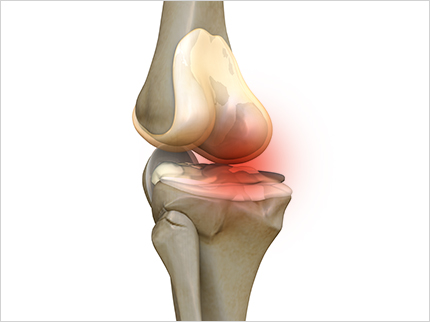

콘드로이친 효능 1. 연골 마모 예방

콘드로이친의 가장 큰 효능은 바로 연골 감소 예방입니다. 콘드로이친은 연골에 영양분을 공급하는 역할을 합니다. 연골에 충분한 영양분들 공급하여 연골의 탄력과 힘을 보충하여 연골이 마모되는 것을 예방해 줍니다. 한 실험울 통해서 콘드로이친을 일정하게 섭취한 사람과 아닌 사람의 연골 마모 속도가 2배 이상 차이가 난다는 결과가 있습니다.